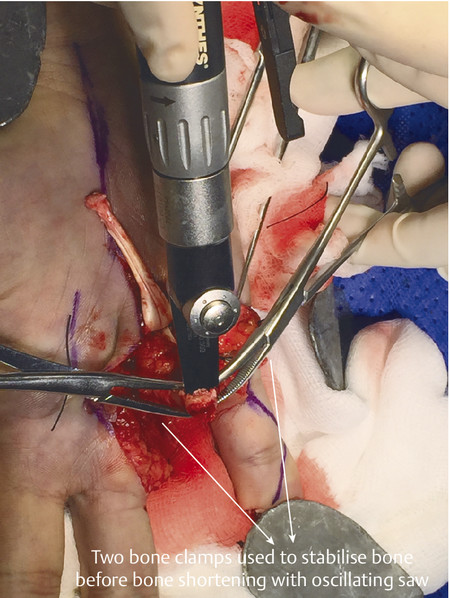

Fig. 12.13 Cross-clamping method to stabilize bone before shortening.

Fig. 12.14 90–90 wiring used to bring bone ends together rapidly. This avoids the use of a C-arm during the procedure and is rapid, cheap, and provides excellent bone-to-bone contact.